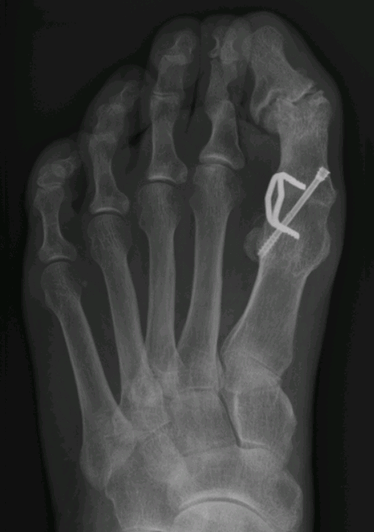

Bij deze vrouw is geleidelijk slijtage en vervorming van het IP gewricht ontstaan, jaren nadat de grote teen operatief was vastgezet.